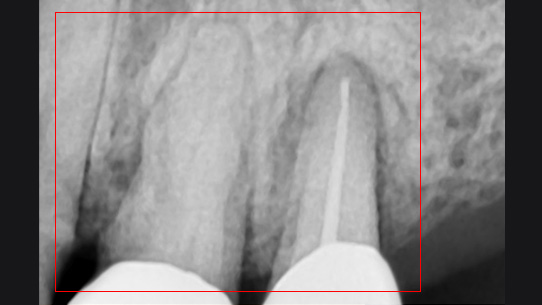

뿌리 주변 염증은 신경관을 소독하고 약재를 삽입하는 신경치료를 시행하였습니다.

신경관 소독

신경관 약재 삽입

약재 주입 후 반응